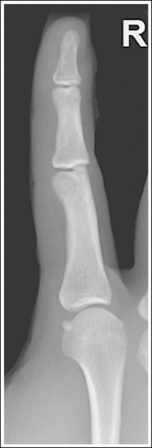

Lateral Finger Projection Analysis

See Figure 4-10 and Box 4-4.

The digit of interest is in a lateral projection. The anterior aspect of the middle and proximal phalanges demonstrates midshaft concavity, and the posterior aspects of the phalanges show slight convexity.

• A lateral finger projection is accomplished by rotating the affected finger 90 degrees from the PA projection (Figure 4-11). Whether the hand is rotated internally or externally to obtain this goal depends on which direction will bring the finger closer to the IR. Typically, when the second and third fingers are imaged, the hand is rotated internally and, when the fourth and fifth fingers are imaged, the hand is rotated externally.

• Distinguishing lateral projection from rotated projection. To understand the difference between a truly lateral digit projection and a lateral projection that is rotated, study a finger skeleton in lateral and PA and AP oblique projections. Note how the midshaft concavity of the middle and proximal phalanges varies as the digit is rotated. In a lateral projection, the anterior aspect of these phalanges is concave, but the posterior aspect demonstrates slight convexity. In PA and AP oblique projections, both sides of the middle and proximal phalangeal midshafts demonstrate concavity, but the side toward which the anterior surface is rotated demonstrates a greater degree of concavity than the side toward which the posterior surface is rotated. The soft tissue width at either side of the phalanx also changes in the lateral and PA and AP oblique projections. More soft tissue is present on the side of the phalanges toward which the anterior surface is rotated (see Image 7).

No soft tissue overlap from adjacent digits is present.

• Flex the unaffected fingers into a tight fist, allowing the finger of interest to remain extended. To visualize the proximal phalanx, it may be necessary to extend the affected finger with an immobilization device or to tape the unaffected fingers away from the affected finger. If the unaffected fingers are not drawn away from the proximal phalanx of the affected finger, they will be superimposed on the area, preventing adequate visualization (see Image 8). An immobilization device should not be used to extend the finger if a fracture is suspected and the device causes stress to the fractured area (see Image 9).

The IP joints are visible as open spaces, and the phalanges are not foreshortened.

• The IP joints are open, and the phalanges are demonstrated without foreshortening as long as the finger was positioned parallel with the IR and the central ray was perpendicular to and centered with the PIP joint.

• When the third and fourth digits are imaged, they are positioned at a greater OID than the second and fifth digits. To keep the third and fourth digits parallel with the IR, it may be necessary to place an immobilization device beneath their distal phalanges. When a finger is not positioned parallel with the IR and perpendicular to the central ray, the IP joint spaces are closed and the phalanges are foreshortened.

The PIP joint is at the center of the exposure field. The distal, middle, and proximal phalanges and the metacarpal head of the affected digit are included within the collimated field.

• Center a perpendicular central ray to the PIP joint to place it in the center of the image. Open the longitudinal collimation to include the distal phalanx and the metacarpal head. Transversely collimate to within 0.5 inch (1.25 cm) of the finger skin line.

Concavity is demonstrated on both sides of the middle and proximal phalangeal midshafts, indicating that the finger was not adequately rotated for this image.

The unaffected fingers were not flexed enough to prevent soft tissue or bony superimposition of the affected digit's proximal phalanx.

Tightly flex the unaffected fingers away from the affected finger. Hyperextending the affected finger with an immobilization prop may also help increase demonstration of the proximal phalanx if a fracture of this area is not suspected.